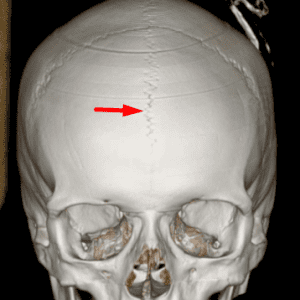

3D reconstruction demonstrating bilateral enlarged parietal foramina

Enlarged Parietal Foramina

Mimicking pathology